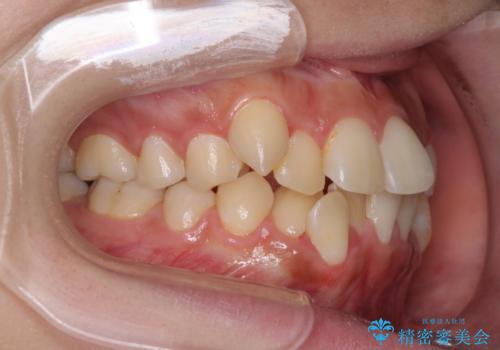

- 八重歯やデコボコをインビザラインで治療したいとのことで来院された患者様です。

インビザライン単体で治療を行うには叢生が強いと判断されたため、事前にワイヤー装置で抜歯矯正を行い、ある程度改善してからインビザラインにて仕上げていくこととしました。